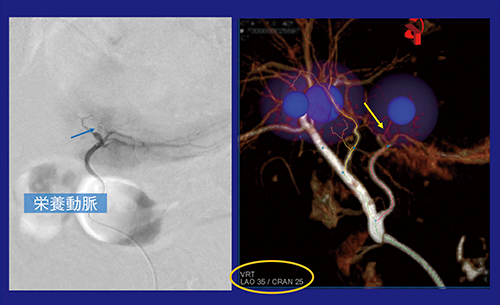

1.syngo Embolization Guidance

HCCに対するTACEの主な治療手段としては,リピオドールを使うconventional lipiodol-TACE(c-TACE)と薬剤溶出性ビーズを用いたTACE with drug-eluting beads(DEB-TACE)があるが,両者には治療成績に差がなく,使い分けについて明確なガイドラインはない。いずれを選択するにしても,塞栓時には腫瘍の栄養血管を同定することが重要である。シーメンスヘルスケアのIVR-CTでは,栄養血管の同定と塞栓のプランニングを行う“syngo Embolization Guidance(Embolization Guidance)”が利用できる(図2)。Embolization Guidanceでは,Cone Beam CT(DynaCT)画像もしくはCT画像を用いて独自のアルゴリズムで栄養動脈を自動検出し,その走行ルートをX線透視画像上に重ね合わせて表示できる。

図2 syngo Embolization Guidance

以下,Embolization Guidanceが有用だった症例を紹介する。症例1は,術前のEOB造影MRIでS4とS2にHCCが見つかりTACEとなった。血管造影では腫瘍濃染像は不明瞭だったが,CTAPとCTHAでは造影MRIに一致して,早期濃染と後期相でのwashoutが認められ,さらに新たなHCCも見つかった。Embolization Guidanceでターゲットを設定すると1cmのマージンをつけて抽出され,栄養動脈の候補がピックアップされる(図3)。過塞栓を避けるため,血管を3本に絞りTACEを行った。S2領域のHCCは,やはり血管造影像では腫瘍濃染は,はっきりと確認できなかったが,Embolization Guidanceで示された角度で撮影すると栄養血管が描出され,カテーテルを進めて超選択的なc-TACEが施行できた(図4)。

TACEにおけるEmbolization Guidanceの有用性は,栄養動脈を効率良く検出して超選択的TACEが可能であり,経験の浅い若手のIVR医でも一定レベルのTACEを行えることである。また,アプリケーションの使い勝手が良く,手技の正確性の向上と時間短縮が期待できる。さらに,あらかじめ透視画像の角度が把握できるので血管撮影の反復を回避し,被ばく線量の低減にもつながる。3D画像で検出,同定した栄養血管の走行ラインは透視画像上に重ね合わせることができ,ガイドワイヤやカテーテル操作のガイダンスとしても有用性が高いと感じられた。